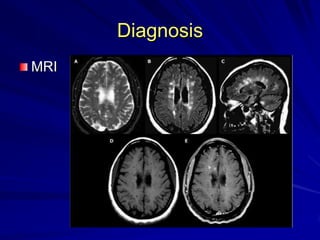

Diagnosis

MRI